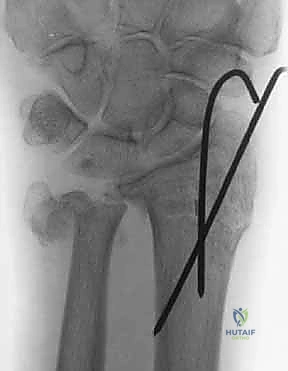

ثانياً: العلاج الجراحي (Surgical Intervention)

متى يقرر الدكتور هطيف ضرورة التدخل الجراحي؟

1. عدم الاستقرار (Instability): إذا كان المفصل الزندي الكعبري البعيد (DRUJ) غير مستقر بعد تثبيت كسر الكعبرة.

2. الانزياح (Displacement): إذا كان الكسر في قاعدة الناتئ الإبري منزاحًا بأكثر من 2 ملم.

3. الكسور المفصلية: أي كسر يخل بتطابق السطح المفصلي لرأس الزند.

4. الكسور المفتتة: في الجزء الكردوسي التي تؤدي إلى قصر عظم الزند.

5. الكسور المفتوحة (Open Fractures): حيث يبرز العظم من الجلد، وتتطلب جراحة طارئة لتنظيف الجرح وتثبيت الكسر لمنع العدوى.

خطوات التدخل الجراحي الدقيق مع الأستاذ الدكتور محمد هطيف

تُعد جراحات المعصم والزند من الجراحات الدقيقة التي تتطلب مهارة عالية، وهو المجال الذي يتفوق فيه الأستاذ الدكتور محمد هطيف بفضل استخدامه لتقنيات الجراحة المجهرية (Microsurgery) والأدوات الجراحية ذات التقنية العالية.

يقوم الدكتور هطيف بدراسة الأشعة المقطعية ثلاثية الأبعاد بدقة، ويختار نوع وحجم الصفائح المعدنية (Plates) والمسامير (Screws) المناسبة لكل مريض بناءً على حجم العظم ونوع الكسر.